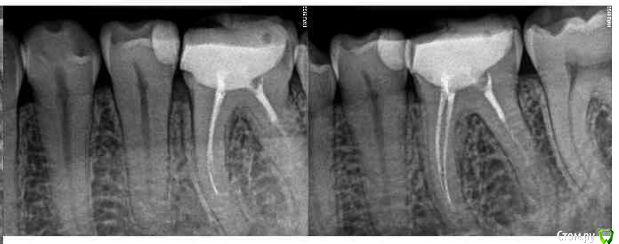

alex2016 Опубликовано 23 апреля, 2016 Поделиться Опубликовано 23 апреля, 2016 Добрый день, Сегодня был у стоматолога в профилактических целях. Т.к. нахожусь в США, то насчитали на ремонт 2600$ (учитывая страховку), т.к. 2600 тратить не сильно горю желанием хочу посоветоваться. Вопрос #1. В одном из зубов (его назвали №19 вроде как, снимок 1) врач обнаружил абсцесс. В этом зубе делали депульпирование и врач сказал, что депульпирование было сделано не до конца и на снимке это видно, т.е. они хотят заново вскрывать канал и заливать его (оба). К тому же он сказал, что в канале застрял кончик сверла (тут не уверен что это называется именно сверло) и его придётся доставать, возможно со стороны десны, если традиционным методом сделать это не получится. Абцесс он мне показал на снимке как небольшое затемнение на челюсти. Зуб не болит и кроме того, что между ним застряёт еда и он сам выглядит не презентабельно ничем не мешает, врач предлагает ставить коронку. Насчёт коронки возражений нету, т.к. еда застряёт и зуб выглядит не презентабельно, хотя в глаза это не бросается т.к. это моляр, а вот насчёт абсцесса я бы хотел уточнить здесь и получить второе мнение. Вопрос #2. Доктор предлагает поставить коронку на зубе #30, картинка #2. Хотя на зубе и достаточно большая пломба, он не выглядит не презентабельно и абсолютно не беспокоит, конечно, он выглядит чуть хуже обычного зуба, но гораздо лучше зуба #1. Сам я склоняюсь к тому, что пока с этим зубом делать ничег не нужно, но второе мнение хотелось бы всё-таки выслушать. Вопрос #3. Доктор предлагает удалить верхние зубы мудрости, т.к. они оказывают давление на дёсны или ещё куда-то там. Здесь я склоняюсь к тому, что он может быть прав насчёт верхнего зуба, потому что у меня там периодически застряёт еда между десной и самим зубом и вызывает неприятные ощущения, правый верхний зуб мудрости абсолютно никаких негативных ощущений не вызывает. Есть ли возможность избавиться от застрявания еды между зубом и десной (это происходит сзади-справа) без удаления зуба? Можно ли удалять один зуб мудрости, а не оба? Вопрос #4. У меня не правильный прикус из-за которого сточились передние верхние зубы, доктор предлагает удалить два верхних зуба, которые идут за клыками, подтянуть верхние передние зубы вперёд и поставить на них коронки, чтобы вернуть хороший прикус и эстетику (сейчас при закрытом рте расстояние между передними зубами верхней челюсти и нижней примерно в 1см). Вся эта процедура займёт кучу времени, т.к. придётся ставить брекет систему и удалять зубы. В клинике в Киеве мне тоже предлагали такой вариант. Зубы хочу сделать, чтобы улыбка стала красивее, поэтому вопросы: А. Обязательно ли удалять 2 зуба для этой процедуры?Б. Если удалить два верхних зуба мудрости, не отодвинутся ли зубы назад сами по себе?В. Хороший ли вариант ставить коронки на абсолютно здоровые, но немного сточенные зубы дли улучшения эстетики? Возможно зубы можно просто нарастить?Г. Не повлияет ли удаление двух зубов на положение верхней губы? При закрытом рте отклонений в прикусе особо не заметно. Благодарю за ответы. Ссылка на комментарий

DmitrySH Опубликовано 23 апреля, 2016 Поделиться Опубликовано 23 апреля, 2016 Вопрос 1.Да, ревизия каналов нужна, коронка нужна, инструмента не увидел на снимке, самое интересное срезано.. нужен снимок еще как минимум 5 мм ниже. Ссылка на комментарий

alex2016 Опубликовано 23 апреля, 2016 Автор Поделиться Опубликовано 23 апреля, 2016 (изменено) Вопрос 1.Да, ревизия каналов нужна, коронка нужна, инструмента не увидел на снимке, самое интересное срезано.. нужен снимок еще как минимум 5 мм ниже.Вот сделал скриншот с другой фотографии. Качество какое есть, если нужно могу спросить нет ли у них качества получше, такое впечатление что отсканировали в самом плохом качестве, т.к. то что они мне показывали выглядело более детализировано. вопрос 2.Может быть не коронку, но керамический оверлей очень кстати, и вкладку или пломбу на 5ый зуб перед ним и 5ый над ним.Благодарю. Доктор, почему-то не упоминал об этой возможности, рассказывал только про импланты и коронки. Уточню насчёт этого. 3 вопрос, скорее всего да, но не по снимку об этом рассуждатьДа в плане того, что можно удалять только один зуб, или то, что можно избавиться от проблемы без удаления зуба? Зуб не болит абсолютно и я даже не знал о том, что это зуб мудрости, просто когда я ем орехи или морковку и они попадают между десной и зубом, то десна воспаляется и вызывает неприятные ощущения, вот сейчас абсолютно нормально и зуб не достаёт совсем, но когда доктор смотрел этот зуб я отчётливо понял, что это именно то место, потому что он его немного зацепил своим прибором, т.е. какая-то проблема там есть, но неужели такая мелочь решается только методом удаления зуба? Изменено 23 апреля, 2016 пользователем alex2016 Ссылка на комментарий

DmitrySH Опубликовано 23 апреля, 2016 Поделиться Опубликовано 23 апреля, 2016 По таком снимку тоже наличие/отсутствие инородного тела в канале сложно определить, но факт что требуется лечение.Ваши верхние восьмые зубы не используются по назначению. Можете смело удалять, в функциональном аспекте ничего не потеряете. 1 Ссылка на комментарий